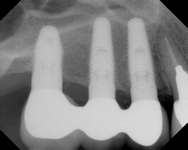

Figure 3A Ridge-split osteotomy with lateral wall expansion. Figure 3B Particulate bone graft was applied, and simultaneous implant placement was performed. Figure 3C The site was covered with barrier membrane.

Figure 3D The site 6 months after surgery, confirming integration. Figure 4A Preoperative radiograph showing ridge resorption.

Figure 4B Radiographic confirmation of graft confinement and incremental addition.

Figure 4C Radiographic view of implant placed simultaneously with sinus bone grafting in site No. 3. Figure 4D Radiographic confirmation of the re-establishment of the sinus floor. Figure 4E Final implant-supported restoration.